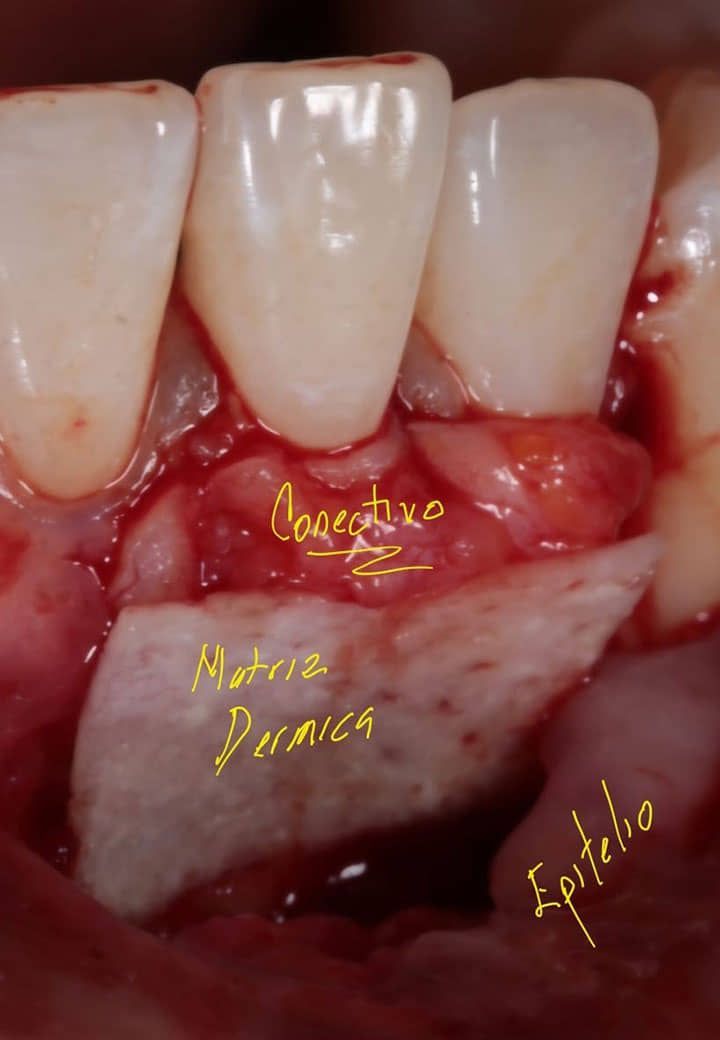

Tratamientos efectivos para combatir la periodontitis

En BIOART, ofrecemos una variedad de tratamientos para combatir la periodontitis. Nuestro equipo de expertos diseñará un plan de tratamiento personalizado para tus necesidades.